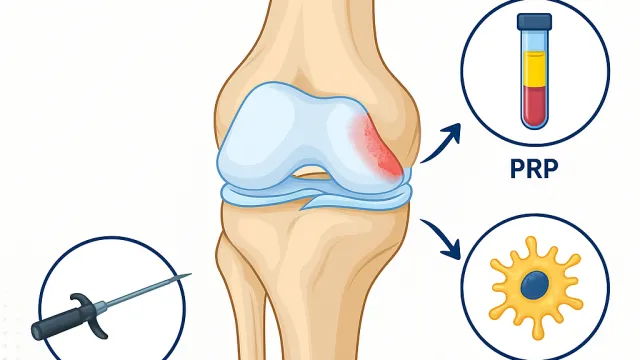

Devamını OkuPRP (Platelet Rich Plasma – Trombositten Zengin Plazma), hastanın kendi kanından elde edilen ve yoğun miktarda iyileştirici hücre ve büyüme faktörü iç...